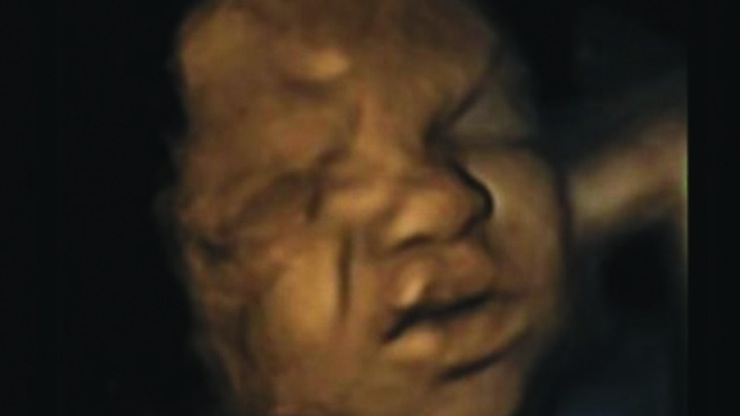

Foetuses in the womb appear to flinch while their mother is smoking, new British research using ultrasound shows.

The captured images show foetuses cringing and touching their faces as their mothers smoke, yet researchers said facial touching should tail off as babies develop in the womb.

The mothers were scanned four times each with high definition ultrasound between the 24th week and the 36th week.